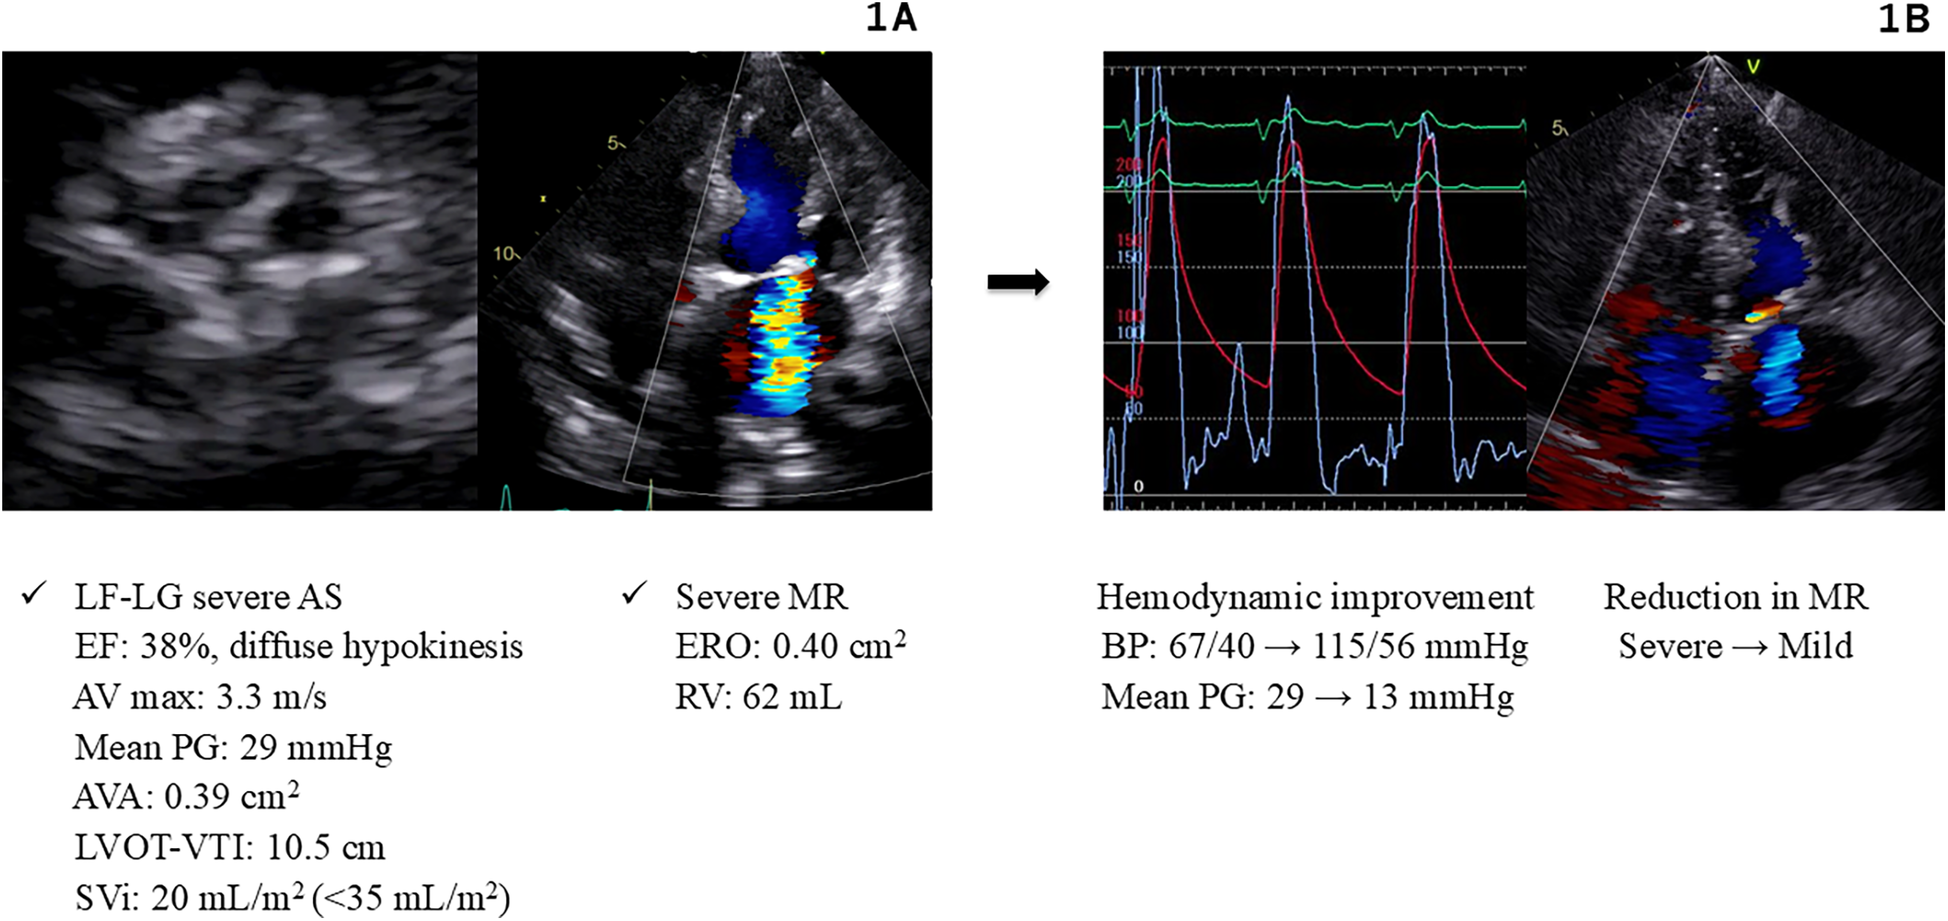

A 92-year-old Japanese female with a medical history of hypertension and diabetes was admitted to our cardiovascular intensive care unit for ADHF. On admission, her vital signs were as follows: blood pressure, 103/65 mmHg; heart rate, 160 beats/min; and peripheral oxygen saturation, 95%, while receiving supplemental oxygen at 10 L/min. Blood tests showed an elevated high-sensitivity troponin T level of 0.243 ng/ml. Chest radiography revealed a cardiothoracic ratio of 66% and pulmonary congestion. Electrocardiography (ECG) showed atrial fibrillation with a heart rate of 150 beats/min and poor R-wave progression. Echocardiography revealed diffuse hypokinesis with a reduced left ventricular ejection fraction (LVEF) of 38%, aortic valve calcification, and severe mitral regurgitation (MR). The aortic valve peak velocity was 3.3 m/s, and the mean PG was 29 mmHg; however, the aortic valve area (AVA) was markedly low at 0.39 cm2 (calculated using the continuity equation), and the stroke volume index was also low at 20 ml/m2, suggesting LF-LG severe AS (Figure 1A).

Figure 1

Hemodynamics and images in Case 1. (A) Echocardiography on admission (Case 1). (B) Hemodynamic improvement after BAV and Impella support (Case 1). AS, aortic stenosis; AV, aortic valve; AVA, aortic valve area; BAV, balloon aortic valvuloplasty; BP, blood pressure; EF, ejection fraction; ERO, effective regurgitant orifice; LF-LG, low flow low gradient; LVOT-VTI, left ventricular outflow tract velocity time integral; MR, mitral regurgitation; PG, pressure gradient; RV, regurgitant volume; SVi, stroke volume index.

The cause of CS was considered to be non-ST-elevation myocardial infarction associated with LF-LG severe AS, severe MR, and ischemic heart disease. Consequently, we planned to improve hemodynamics through an intervention for severe AS by performing BAV using an 18-mm Tyshak balloon (Cardinal Health Japan, Tokyo, Japan). Immediately after the procedure, the patient experienced cardiac arrest owing to pulseless electrical activity. Cardiopulmonary resuscitation was promptly initiated, and an Impella 2.5 device was implanted, resulting in the stabilization of blood pressure at 115/56 mmHg. These procedures led to a reduction in the aortic valve PG from 29 to 13 mmHg, and the MR improved significantly (Figure 1B). Subsequently, percutaneous coronary intervention (PCI) was performed and drug-eluting stents (Xience Alpine; Abbott Vascular, Santa Clara, CA) were implanted into the right coronary artery and left anterior descending artery. These interventions stabilized the patient's hemodynamics, allowing discontinuation of catecholamines. The Impella device was removed on day 5, and the patient was extubated on day 9. Thereafter, the patient maintained compensated heart failure (HF) and stable hemodynamics with oral therapy alone. The heart team evaluation deemed the patient to be at a high surgical risk (STS score: 12.8%, Clinical Frailty Scale score: 4, Katz Index: 4), and TAVR was recommended. Elective TAVR with a 23-mm SAPIEN 3 valve (Edwards Lifesciences, Irvine, CA) was successfully performed on day 19.